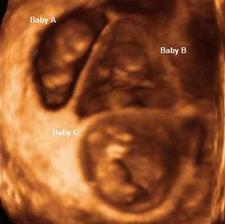

Vajíčko ve vejcovodu čeká zhruba 12 až 24 hodin na příchod spermií. V ejakulátu je v průměru 250 milionů spermií, z toho pouze zhruba 400 se dostane až k vajíčku ve vejcovodu, přičemž cesta z pochvy do vejcovodu trvá spermiím až 10 hodin. Obvykle pouze jedna spermie uspěje a pronikne po zhruba 20 minutách snahy do vajíčka. Tím dojde ke vzniku oplodněného vajíčka, tzv. zygoty. V příštích 10 až 30 hodinách dochází ke splynutí genetických informací vajíčka a spermie. Pohlaví dítěte je určeno již v této chvíli – pokud spermie nese chromozom Y, narodí se chlapec, pokud chromozom X, narodí se dívka.